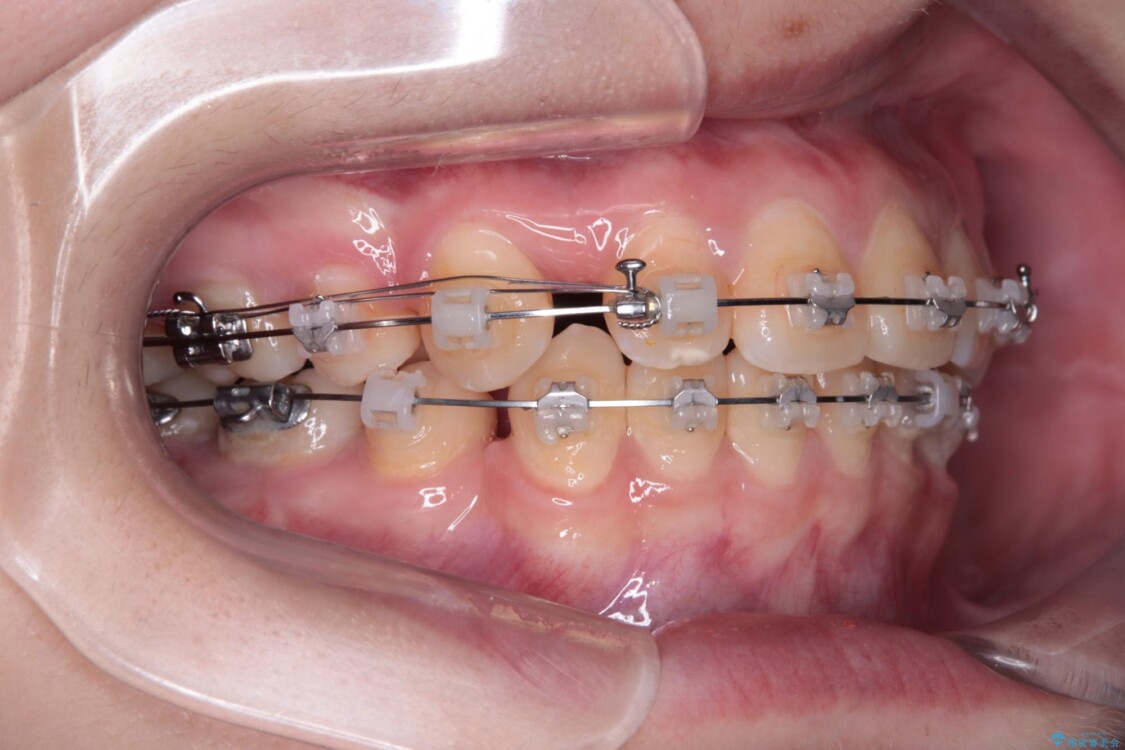

治療途中

• 転勤でも安心して治療継続 抜歯スペース閉鎖と深い噛み合わせ改善のワイヤー矯正 治療途中画像